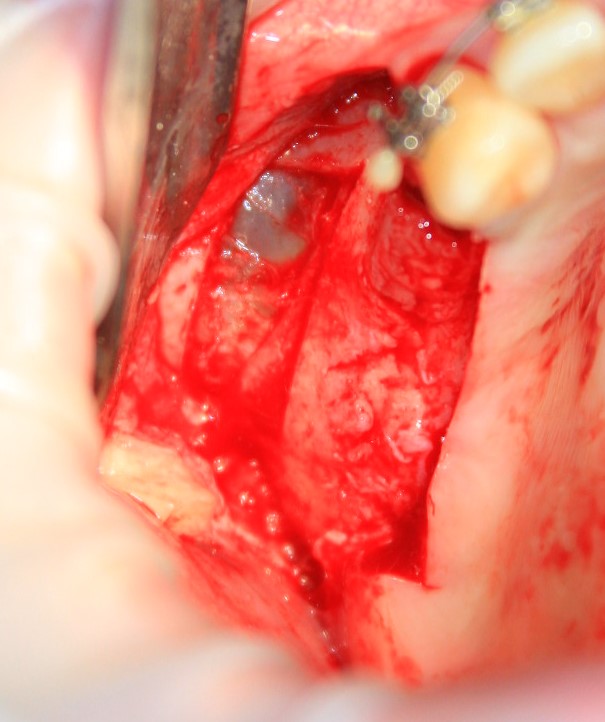

Кстати, обрати внимание на ширину альвеолярного гребня (левая картинка). Она чуть меньше 3 мм. Это объясняет, почему я засомневался в возможности установки имплантатов одновременно с остеопластикой. Понятно и без КЛКТ.

Наперво, мне нужно удалить разрушенный зуб и получить костный аутотрансплантат.

Возвращаемся к основной операционной области. Еще раз посмотрим на альвеолярный гребень, поофигеваем от его ширины и моих грандиозных планов: